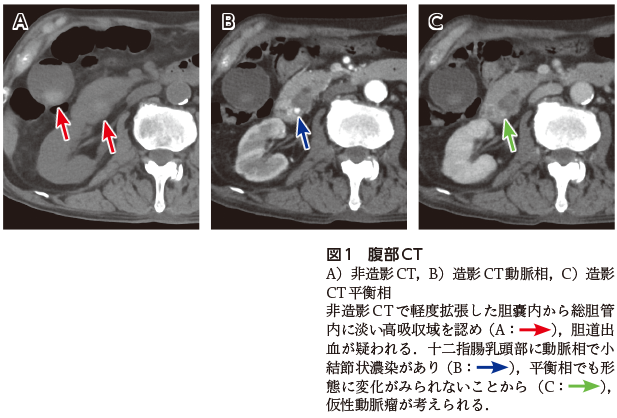

腹部CT(図1)にて十二指腸乳頭部仮性動脈瘤による胆道出血と診断され,緊急血管造影検査を施行した(図2).前上膵十二指腸動脈の仮性動脈瘤が明らかとなり金属コイルを用いた塞栓術が施行された.その後,再出血なく,貧血は改善し退院となった.

図2